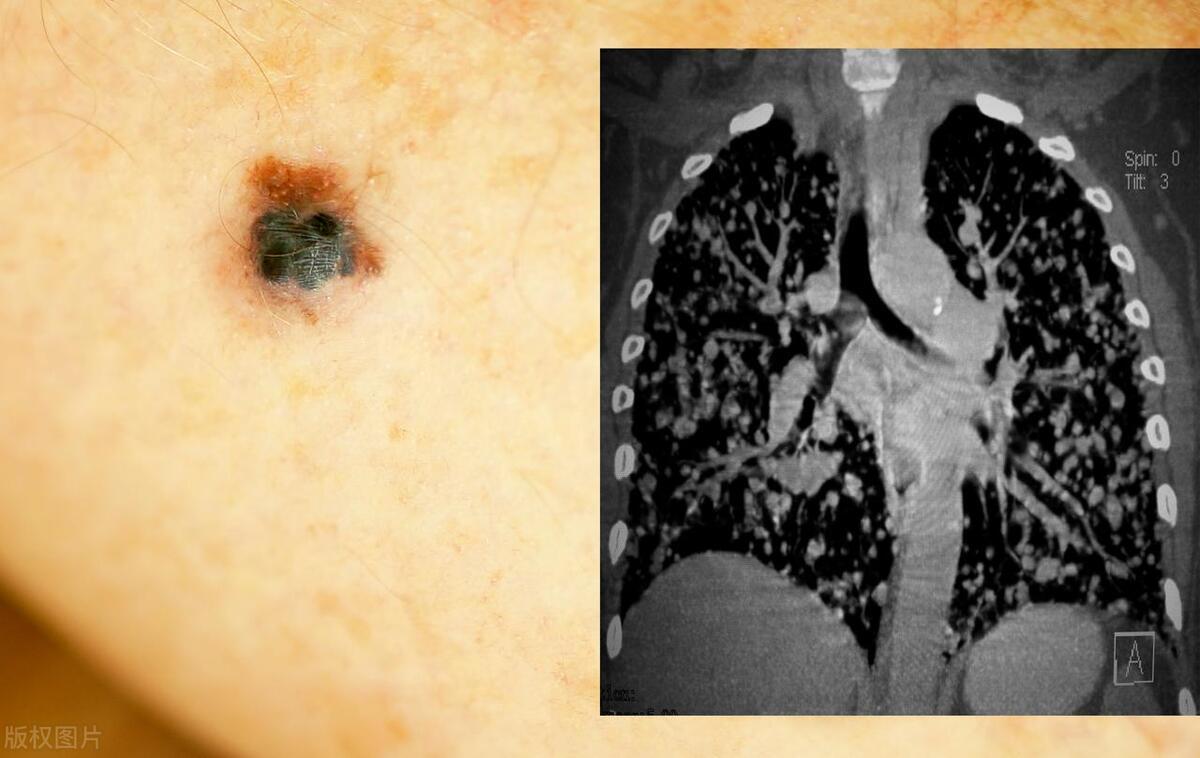

惡性黑色素痣初期的識別與應(yīng)對,惡性黑色素痣初期識別與防治攻略

摘要:惡性黑色素痣初期識別與應(yīng)對至關(guān)重要。初期癥狀包括皮膚出現(xiàn)黑色或棕色的痣,形狀不規(guī)則,邊緣不整齊,顏色不均等。若出現(xiàn)這些癥狀,應(yīng)及時就醫(yī)進行專業(yè)檢查。治療方法包括手術(shù)切除、放療和藥物治療等。早期識別和治療有助于提...